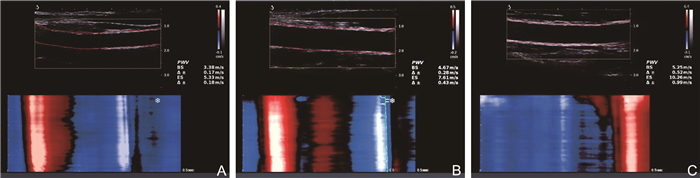

Evaluation of ultrafast pulse wave technique in subclinical atherosclerosis in SLE and its clinical correlates

WANG Xing, LU Fang, SHI Yan, LI Yang, XIE Changhao

2025, 23(7): 1192-1195. doi: 10.16766/j.cnki.issn.1674-4152.004095

325 2

Abstract:

Objective  To make an assessment of vascular elasticity in patients with systemic lupus erythematosus (SLE) at varying levels of disease activity using ultrafast pulse wave technique, and to investigate associated clinical risk factors.  Methods  A total of 116 SLE patients admitted to the First Affiliated Hospital of Bengbu Medical University from October 2020 to April 2024 were selected. Patients were divided into a mild activity group (n=57) and a moderate-to-severe activity group (n=59) according to SLE disease activity index 2000. Additionally, 45 healthy adults were included as the control group. Carotid intima-media thickness (IMT), pulse wave velocity at the beginning of systole (PWV-BS), and pulse wave velocity at the end of systole (PWV-ES) were measured in each group. Clinical data of each group were recorded and analyzed. Carotid artery parameters and clinical data of the three groups were compared to analyze the correlation between PWV parameters and various indicators.  Results  Both PWV-BS and PWV-ES showed significant differences among the three groups, following the pattern: moderate-to-severe activity group > light activity group > control group (P < 0.05). PWV-BS was positively correlated with common carotid artery IMT (r=0.315, P < 0.001), systolic blood pressure (r=0.190, P=0.041), and diastolic blood pressure (r=0.191, P=0.040). PWV-ES was positively correlated with carotid bifurcation IMT (r=0.274, P=0.003), common carotid artery IMT (r=0.361, P < 0.001), and diastolic blood pressure (r=0.252, P=0.006).  Conclusion  The reduction in carotid artery elasticity in SLE patients occurs significantly earlier compared to healthy individuals. Ultrafast pulse wave is valuable, time-independent, and objective tool for quantitative assessing early vascular changes in patients with SLE, thus facilitating the early detection and clinical management of atherosclerosis.